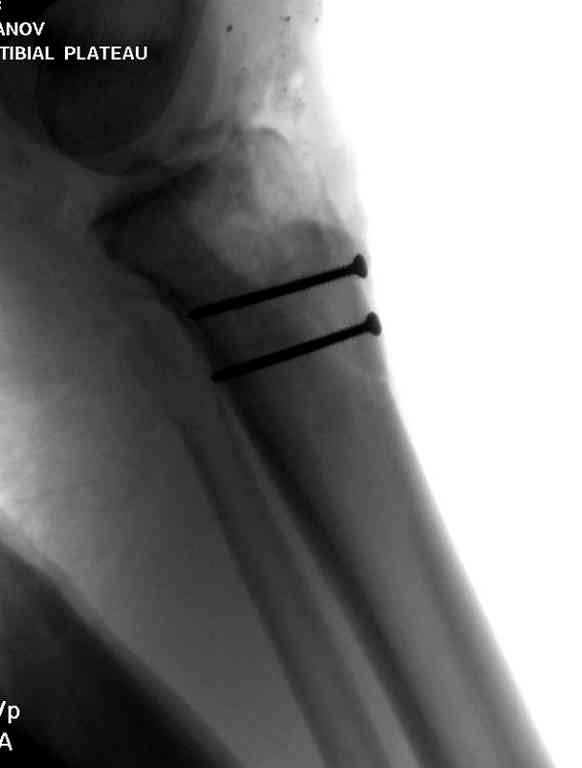

Здесь применение материала Plexur http://www.plexur.com для пластики при дефектах кости у больной с огнестрельной раной латерального тибиал плато с повреждением малоберцового нерва. Несмотря на интактный медиальный мышелок, для профилактики от вальгуса установлен АВФ и сделана ангиограмма.

После нескольких обработок и вакуумирования, поэтапно сделана фиксация тибиального бугра шурупами. И окончательную фиксацию закончили латеральной пластиной для тибиал плато и установкой пластического материала.